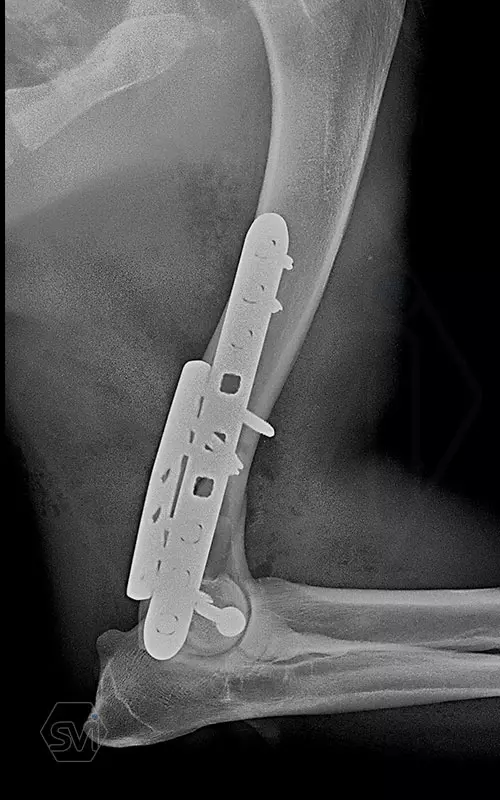

Nightmare for all of us: diastal humeral Y-fracture in a large active dog (German Shepherd)

The damaged area was exposed laterally and medially, and 2 locking plate were used: a large polyiaxial straight plate made with 3.5 mm screws, and a small polyaxial plate laterally with 2.7 mm screws.

The intercondylar fragments were fixed with 3.5mm lag screw with a washer under the head.

The dog was already using his leg very nicely at control 1 month post op., barely limping. In such a case, the advantages of locking systems (distal short screws are also permanently fastened) and polyaxiality (positioning the screws of the opposing plates so that they do not interfere with each other, and avoiding the screw insertion into the joint or fracture line) are really very helpfull.